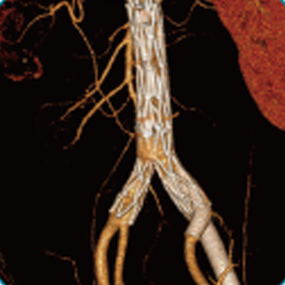

Aegis®/定海石™分叉型大动脉覆膜支架及输送系统

Aegis®/定海石™分叉型大动脉覆膜支架及输送系统适用于瘤体累及髂总动脉的腹主动脉瘤的治疗。